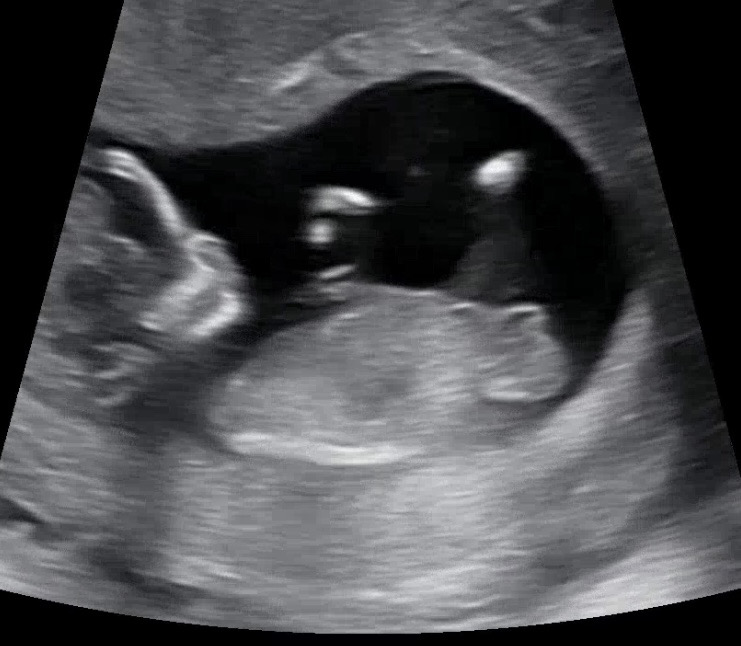

ㅠㅠ각도법이게 맞나요???어렵네요

어떻게 보이시나요? 12주차5일에 찍은거에요!

딸?.? 같아용